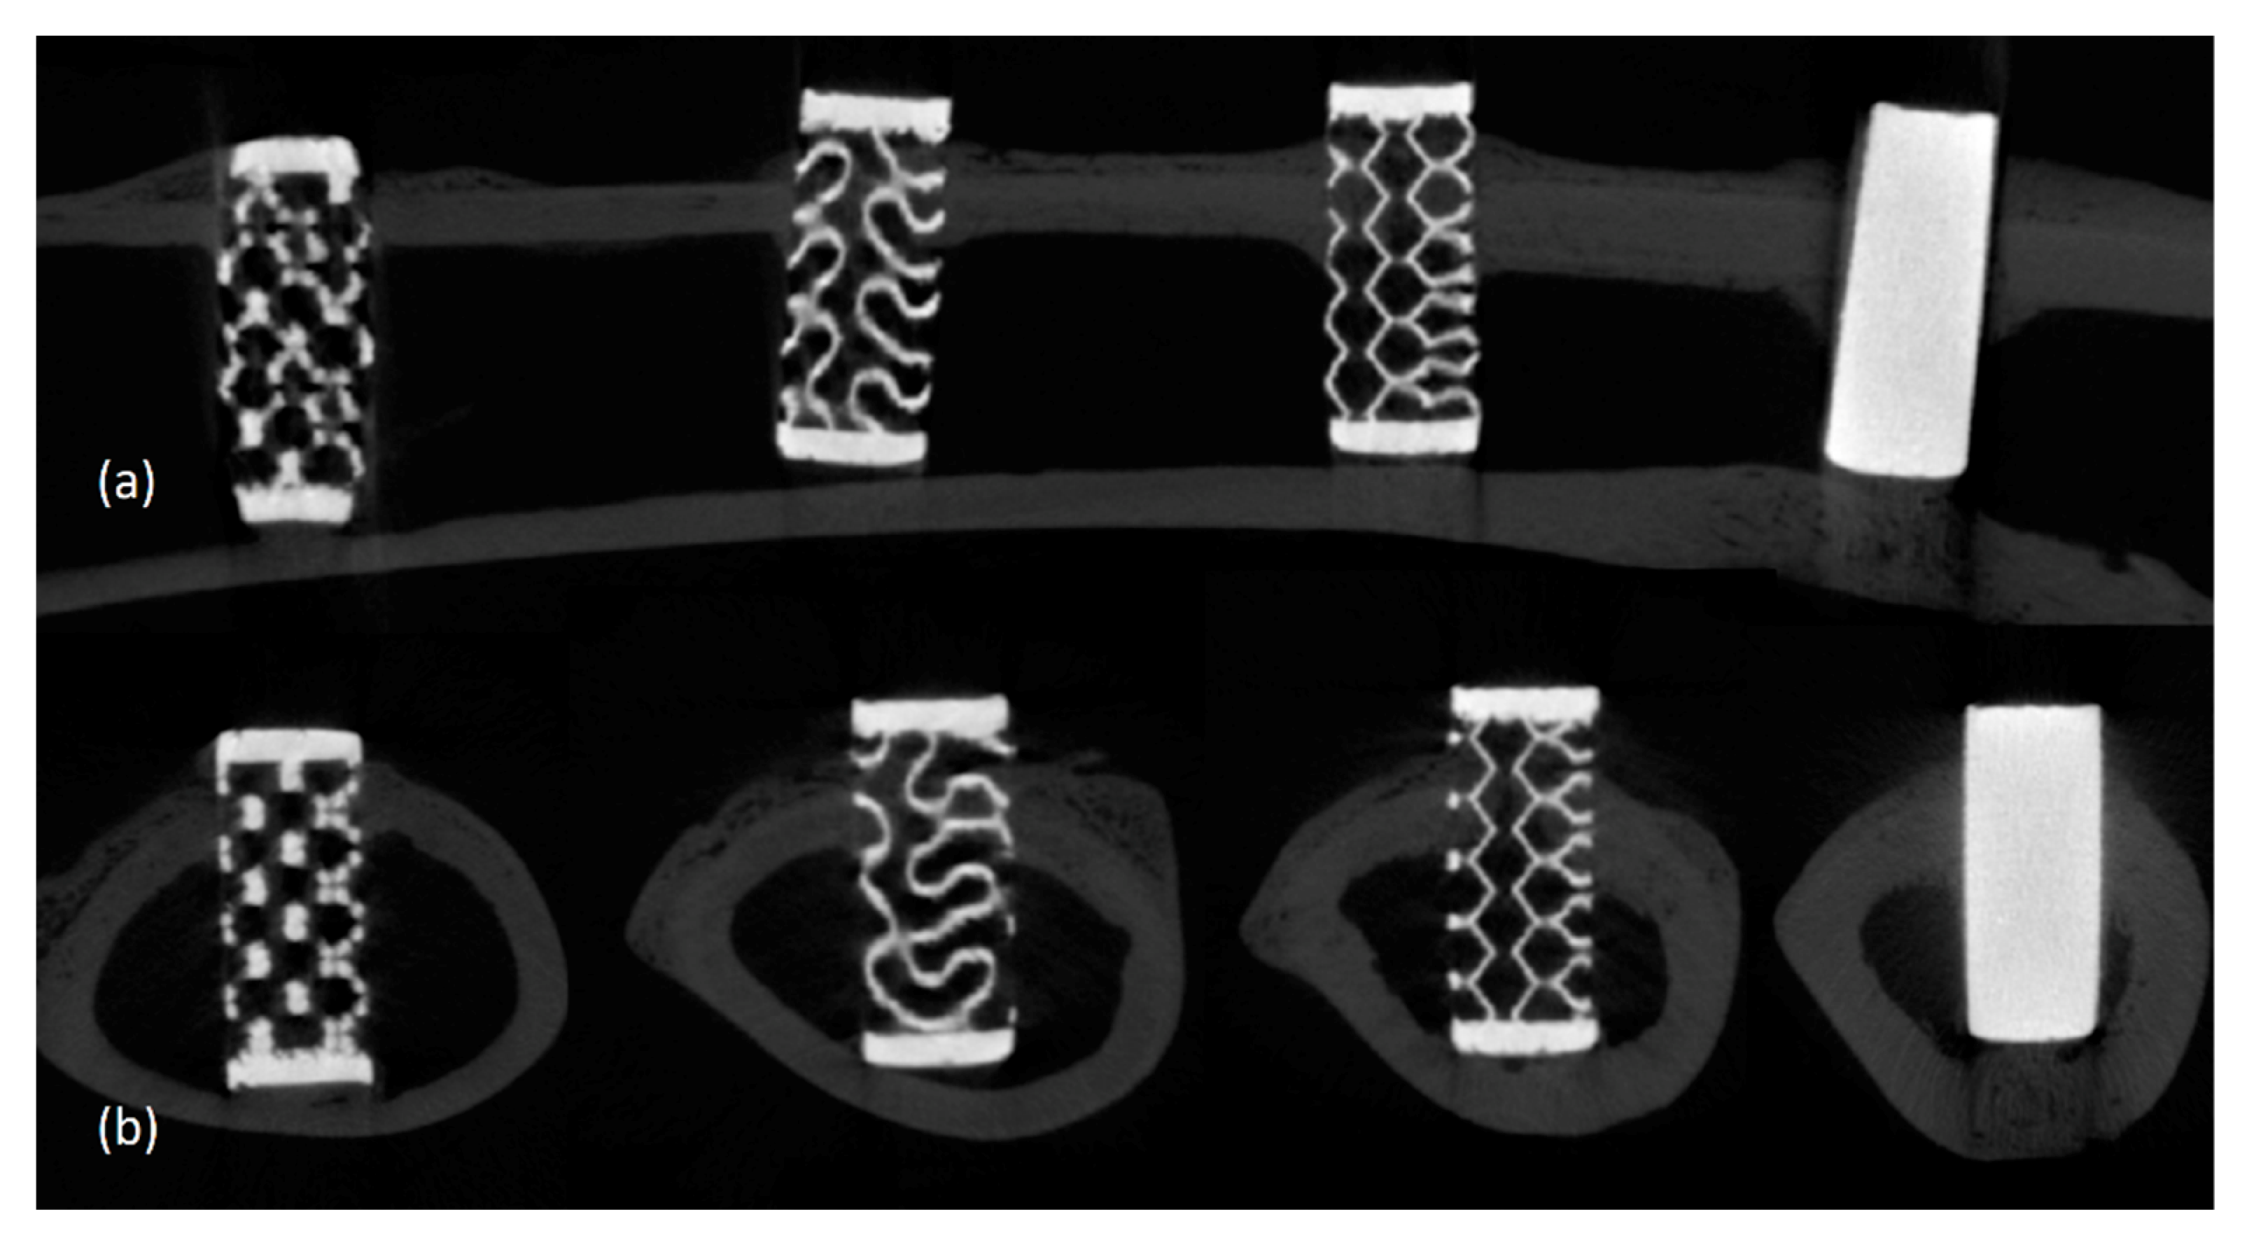

2.4. Micro-CT Imaging and Volumetric Analysis

3.2. Radiological Findings